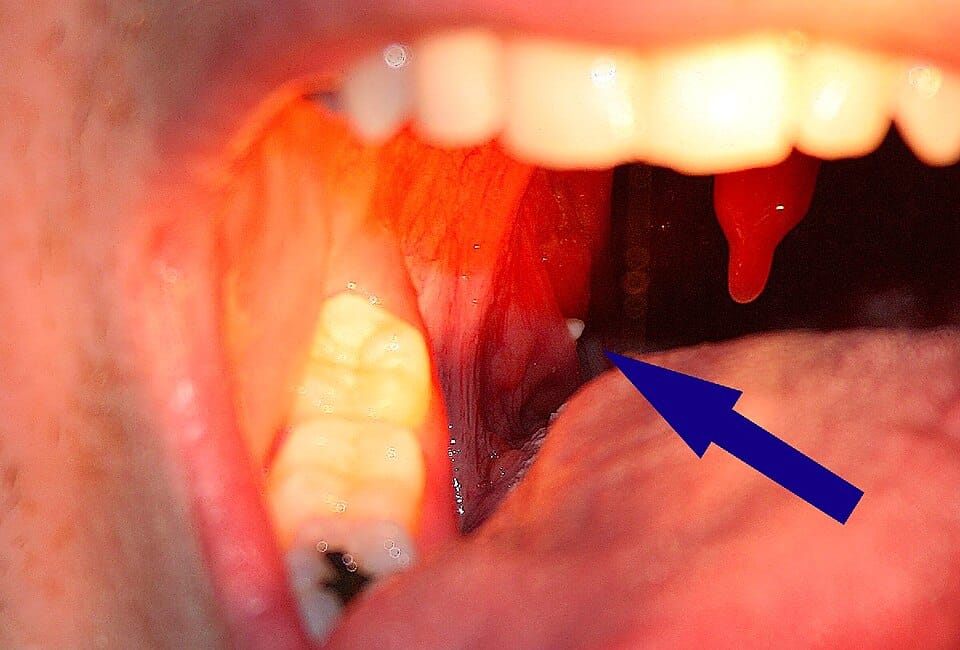

Ces petits amas, souvent comparés à des cailloux miniatures, résultent d’un mélange de débris alimentaires, cellules épidermiques et bactéries. Les cryptes amygdaliennes – ces minuscules cavités naturelles – agissent comme des pièges à résidus. Avec le temps, ces accumulations se solidifient, prenant une teinte variant du blanc cassé au jaune pâle.

Rassurez-vous : leur présence est généralement sans gravité. Toutefois, elles peuvent occasionner une irritation persistante ou une haleine moins fraîche. Un désagrément qui pousse souvent à s’interroger sur leur origine.

Plusieurs éléments entrent en jeu : anatomie particulière des amygdales, fréquence des infections ORL, ou même sensibilité aux allergies. Certains individus les expulsent naturellement en toussant, tandis que d’autres les découvrent par hasard lors d’un examen buccal.